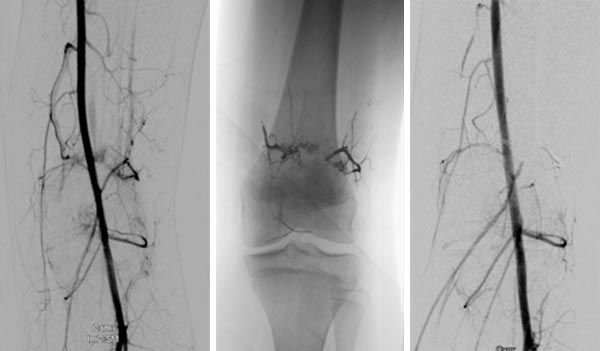

In der DSA vor Embolisation (linkes Bild) finden sich kniegelenksnah multiple feine AVMs. Im Nativröntgenbild nach Embolisation ist das röntgendichte Embolisat zu sehen (mittleres Bild), das die arteriovenösen Fisteln ganz ausfüllt. In der DSA nach Embolisation (rechtes Bild) ist der gesamte Nidus der AVM verschlossen, keine sichtbaren arteriovenösen Fisteln mehr.